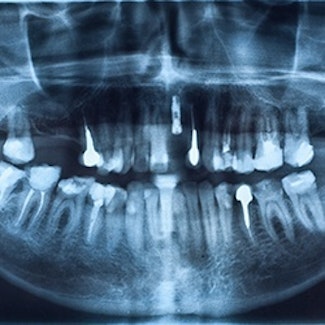

DIGITAL PANORAMIC X-RAYS

A panoramic image is an X-ray that depicts a panoramic view of your mouth – from one side to the other. This image can help the dentist understand the relationship between your teeth, jaws, and occlusion (bite, or how your top and bottom teeth fit together). This image is saved as part of your dental records.